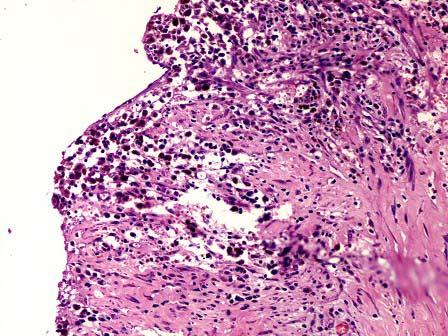

问题 女性,37岁,月经不规则数年,因下腹痛行检查,发现左下腹一包块。行左侧卵巢切除术并送检。大体见卵巢组织间一囊性瘤5cm×4cm×2cm,灰红,切开流出红褐色粘稠液体,囊壁增厚,壁厚12cm。镜下见囊壁增厚,纤维组织增生,无明显内衬上皮,可见含铁血黄素。卵巢组织间见子宫内膜上皮与间质结构(如图)。应诊断为 ( )

选项 A.卵巢巧克力囊肿 B.卵巢黏液性囊腺瘤 C.卵巢交界性黏液性囊腺瘤 D.卵巢黏液性囊腺癌 E.卵泡膜囊肿

答案 A